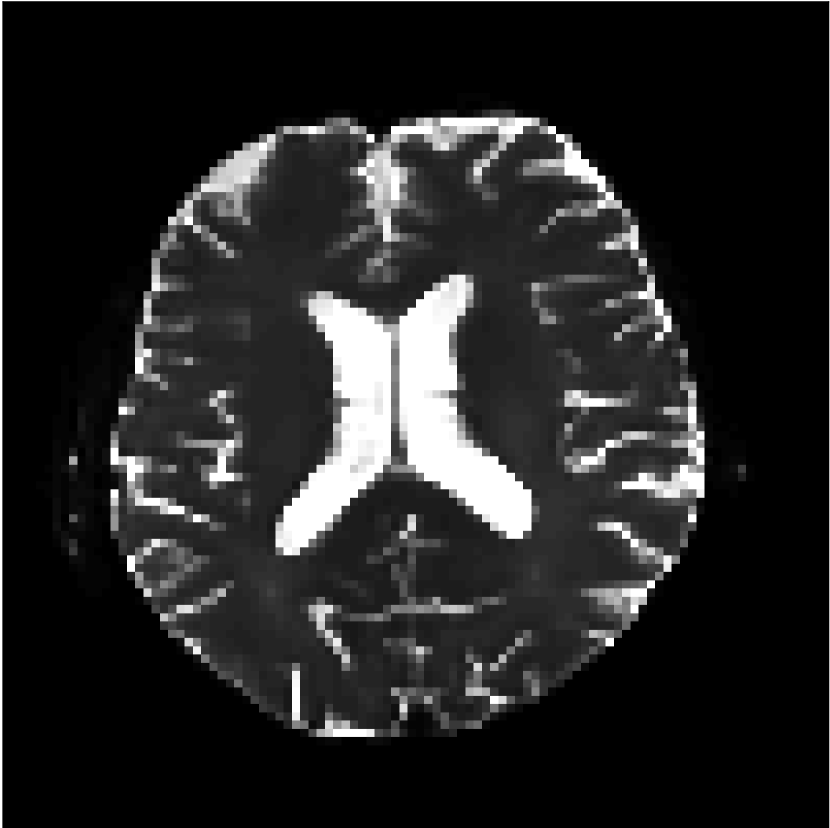

Figure 9 shows parameter maps for the different methods without partial Fourier (No PF) and with 5/8ths partial Fourier (5/8 PF). Mean diffusivities calculated from the raw DWI data (Raw) show notable noise and Gibbs ringing artifacts, while this is substantially removed with the state-of-the-art (SoA) method. However, the state-of-the-art method begins to lose its ability to compensate for the Gibbs ringing and resolution loss when partial Fourier is utilized in the acquisition. The effects of partial Fourier increases are primarily evident in the enlargement of the lateral ventricles and the presence of black lines in the vicinity of the lateral ventricles. The MCNN model is able to compensate somewhat for the ringing effects, but begins to introduce substantial artifacts at the 5/8ths partial Fourier factor, whereas the CCNN model continues to give high-quality mean parameter maps across all PF factors.

Raw

SoA

MCNN

Standard PF

CCNN

MK

Figure 9: Parameter maps from various methods (with CSF masks for FA and MK). At the top are shown the b=0𝑏0b=0 images from Raw, state-of-the-art (SoA), MCNN, standard partial Fourier, and CCNN methods. Rows 2 and 3 show results for mean diffusivity, rows 4 and 5 show results for fractional anisotropy, and rows 6 and 7 show results for mean kurtosis. The SoA method and both deep learning methods perform well without partial Fourier acceleration; however, at the 5/8ths partial Fourier factor, substantial artifacts are present for all methods other than the CCNN method.

Similar trends are observed in the other diffusion parameter maps.